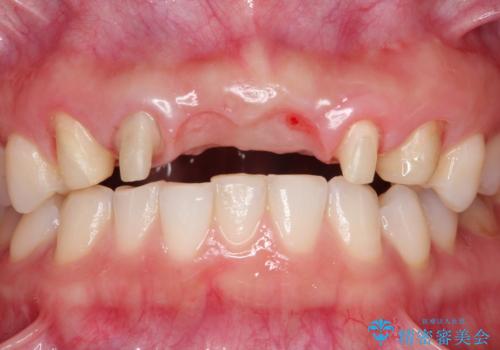

- 数ヶ月前に治療終了したブリッジの歯ぐきの違和感が強く、改善を求めて来院されました。

歯ぐきは著しく腫れ、少し触ると出血してしまうような状態であったためブリッジの再作製・歯周外科を用いた歯肉環境の改善を計画します。